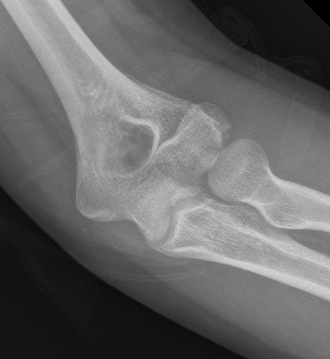

Double arc sign seen on xray

Capitellum + trochlea fractures

In two separate pieces

Capitellar fracture

Capitellum + trochlea fracture

In one piece